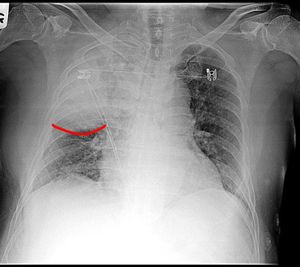

Lung

Fissure

Bulging